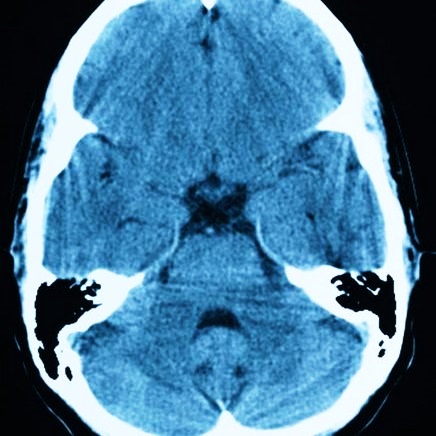

- Ряд острых нарушений внутримозговой циркуляции крови, наступающих после приступа геморрагического либо ишемического инсульта, церебрального паралича тела, субарахноидального кровоизлияния в мозг;

- церебральная киста. Она формируется не на поверхности, а во внутренних слоях головного мозга из-за смерти клеток мозга. Чтобы остановить омертвение мозга, следует своевременно установить причину отмирания этих клеток. Вызвать развитие такой опухоли могут и новые инфекционные очаги, трепанация черепа, слабое снабжение кровью мозга, а также микроинсульты. Если такое новообразование продолжает расти в диаметре, назначается операция;

Если образование находится в левом полушарии, то без лечения снижаются мыслительные и математические способности, затрудняется чтение и письмо, нарушаются функции правой стороны тела. Постишемическая опухоль может нарушать походку и затруднять передвижение, а в очень сложных ситуациях наступает полный паралич.

Без адекватного лечение кистозное образование в мозгу опасно развитием эпилептических припадков, а у больных с кистой в районе ствола может развиваться дизартрия и дисфагия. Если не обращать внимания на кисту промежуточного паруса, дело может закончиться гидроцефалией, синдромом сдавливания структур мозга или кровоизлиянием. Но самым страшным последствием для любого пациента с кистой в мозгу является внезапная смерть.